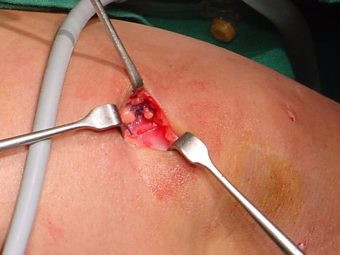

Luxación Habitual de Rótula

Envíado por Dr. Eduardo E. Martínez Melara